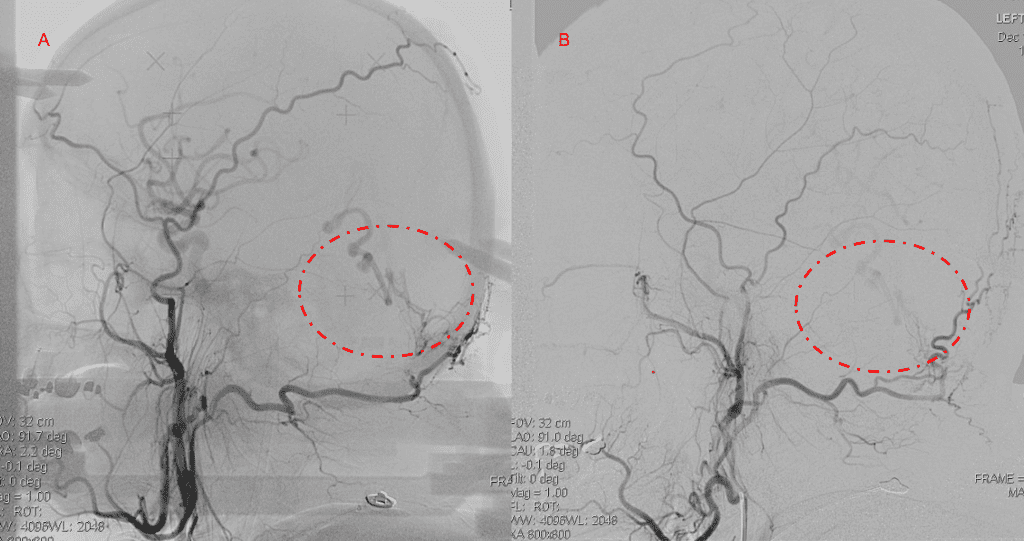

Embolization was successful at immediately reducing the pressure into the Aneurysmal Varix with greater than 90% reduction in A-V shunts. After an intensive period of critical care monitoring and care for her initial brain hemorrhage, she made a near complete recovery with mild intermittent left sided paresthesias and generalized deconditioning. After receiving inpatient and outpatient Acute Rehabilitation, Physical, and Occupational therapy, she completely recovered all of her Activities of Daily Living (ADLs) at 3 months and achieved an modified Rankin Scale (mRS) of 0. On follow-up angiography, small residual low flow A-V shunts were identified and targeted for Gamma Knife Radiosurgery (Figure 5 and 6).

Figure 5. Bilateral ECA Lateral angiograms (A and B) demonstrates small residual indirect supply To the AVM from the bilateral Occipital arteries.

Figure 6. MRI and Catheter Angiograms precisely localize the residual A-V shunts vessels to perform Gamma-Knife Radiosurgery to deliver therapeutic doses to the targets.

Over the 12 to 18 months, she continued to remain event-free and maintain her active independent lifestyle. Delayed angiography over that period confirmed complete obliteration of the Left ECA and Vertebral Artery shunts with near complete obliteration of the Right ECA shunts (Figure 7).

Figure 7. 12 mos follow-up angiograms confirm complete obliteration of the left ECA and Vertebral Supply to the AVM, with a small late-filling component from the right Occipital artery that is markedly Reduced in size and flow (top row). Near complete resolution of the aneurysm and hematoma Is observed on 16 mos post Gamma Knife MRI (bottom row).